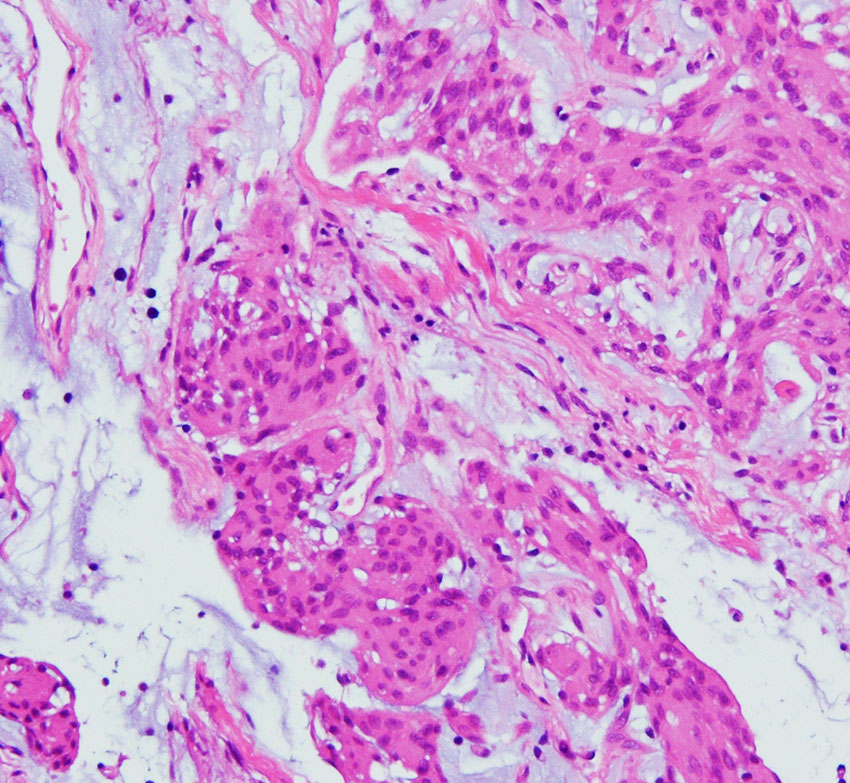

chordoid meningioma WHO grade 2 脊索腫様髄膜腫

この例は鞍結節に発生した髄膜腫で,T2強調画像では高信号が目立ちましたが骨浸潤はなく,一般的なgrade 1 meningiomaとの鑑別はできませんでした。粘液を含む腫瘍で、好酸性の胞体を持つ紡錘形ないし類円形核の細胞がmyxoid / chordoid matrixに浮遊している所見です。腫瘍細胞が固まる部分は典型的な髄膜腫の特徴をよく表す組織構造です。胞体内には空胞変性 vacuolated cells が認められました。MIB-1 5%, EMA (+), Cam5.2 (-)。珍しいタイプで,概して大きな髄膜腫としてテント上に発見され,手術後の再発率は高いのでグレード2とされます。Wangは30例中の5例に再発を見たとしていますから全摘出できればそれほど高い再発割合ではありません。

Castleman’s diseaseをはじめhematological conditions / diseasesとの合併や小児例例が多いとされましたが,実際には特発例,孤発例が多いです。